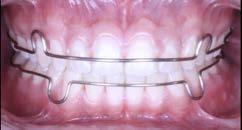

Figura 4. Imagen representativa de una férula flexible en la superficie labial del órgano dental afectado y en los dientes adyacentes. Tomada por el esp. Isidro Valdez Ramírez.

Un método de tratamiento para dientes traumatizados es la ferulización dental (Figura 4), que permite la curación del tejido periodontal y al mismo tiempo protege el diente de lesiones adicionales. La fijación flexible o semirrígida es suficiente para la curación pulpar y periodontal en la mayoría de las TDI, y la fijación rígida solo se recomienda para las fracturas de la raíz cervical. Si la anquilosis no supone un riesgo significativo, se recomienda entre 1 y 2 semanas durante el periodo de fijación. Sin embargo, si las lesiones traumáticas incluyen destrucción del hueso, pueden ser necesarias de 1 a 2 semanas adicionales, y en caso de fracturas de raíz, pueden ser necesarios hasta 4 meses de inmovilización.15

Muchos tratamientos de ortodoncia se realizan en preadolescentes; sin embargo, las lesiones dentales traumáticas son comunes durante los años de la preadolescencia. Los dientes con luxación extrusiva también suelen luxarse lateralmente hacia el lado lingual/palatino, lo que puede provocar una mordida cruzada anterior, lo que provoca una alteración de la oclusión. La Asociación Internacional de Traumatología Dental (IADT) recomienda la reposición de dientes permanentes luxados lateralmente y extruidos, ya sea manualmente o con fórceps, poco después del traumatismo y la estabilización con una férula flexible (Figura 5). Sin embargo, las deformaciones del hueso alveolar en ocasiones forman una barrera para este reposicionamiento dentario. Cuando se retrasa el tratamiento, los coágulos de sangre también pueden bloquear el reposicionamiento de los dientes luxados.18